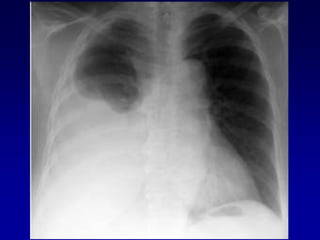

Lesiones Torácicas Potencialmente Fatales

Tipo Tratamiento Inicial

 Hemotórax ABC

Neumotórax Tubo tórax (TDC)

Hemoneumotórax

 Neumotórax abierto ABC

Oclusión

Tubo tórax (TDC)

 Tórax inestable ABC

Ventilación presión positiva